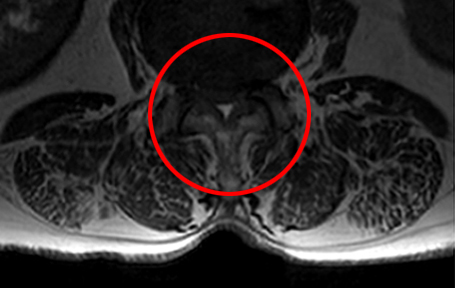

협착증 한방치료로 신경압박이 풀리는 눈에 보이는 증거가 있습니다.